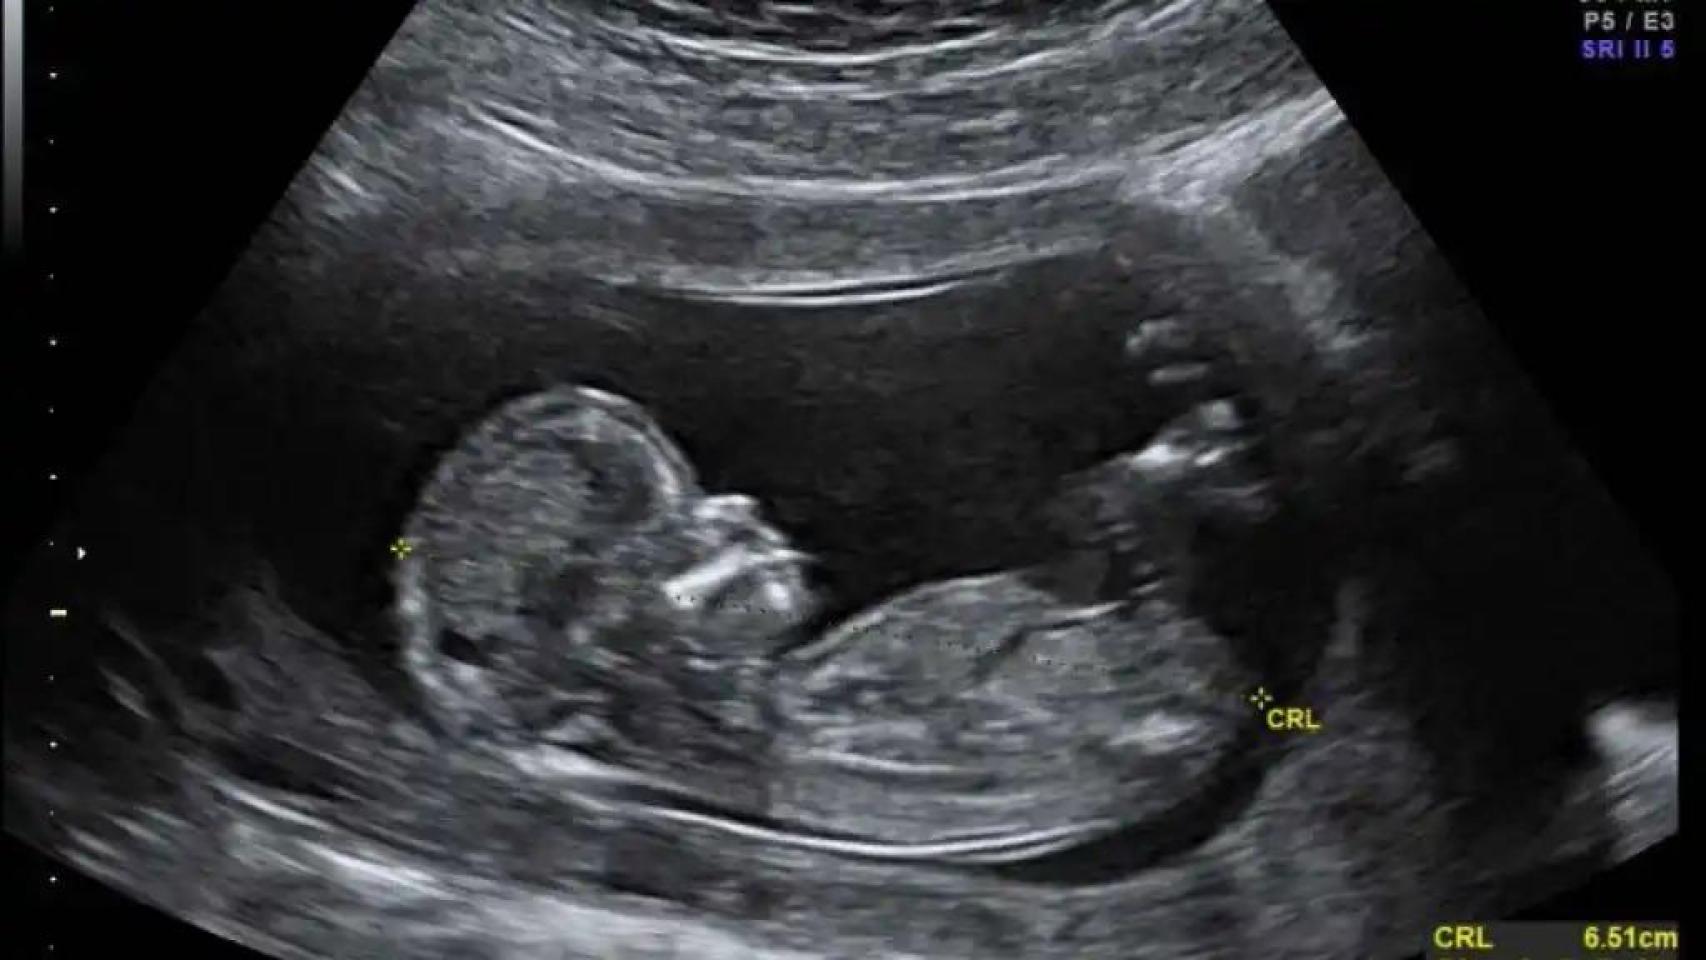

En medicina, cuanto antes se actúe, mejor. Es lo que pensó el personal médico del hospital St. Jude Children's Research, en Memphis (EEUU) cuando supieron que el bebé que llevaba en su seno una mujer embarazada iba a nacer sin ninguna versión funcional del gen SMN1.

La madre ya había perdido un hijo por la misma razón: una enfermedad rara y letal llamada atrofia muscular espinal. Ella fue quien les apremió a empezar a tratar a su bebé antes incluso de que naciera.

Así que la madre comenzó a tomar risdiplam —tiene un coste de alrededor de 300.000 euros anuales pero el laboratorio que lo fabrica lo ofreció de forma gratuita con fines de investigación— desde la semana 32 del embarazo hasta la 38, cuando dio a luz.

Las pruebas de líquido amniótico y sangre umbilical mostraban que el fármaco estaba llegando al útero y pasando al feto. El bebé mostraba un aumento de los niveles de la proteína SMN.